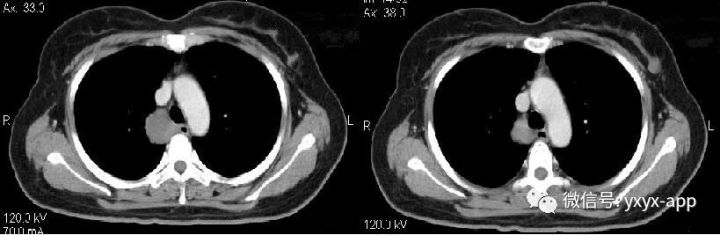

CT值在50-60hu之间

肚肚丫头:右上后纵隔、气管右旁、脊柱前方可见类圆形软组织密度影,与气管及食管均关系,增强后无明显强化,考虑囊肿,起源待定。

CT表现:纵隔旁支气管囊肿其典型形态为圆形、类圆形、水滴形、长条形,偶为分叶状,边缘均清楚锐利,内部密度多较均匀。肺内型表现为单发的气囊肿、液囊肿、液-气囊肿或多发囊肿,边界清楚,囊壁薄而均匀,可合并肺发育不良、肺隔离症、肺气肿及胸廓塌陷等其他肺内畸形。CT值差异较大,多为20~30HU,最高可达80HU,反映囊肿内容物的不同成分,囊肿不与支气管相通时形成含液囊肿,与支气管相通时囊液会全部或部分排出,形成含气囊肿或含气液囊肿。如有感染、出血或囊壁受到刺激可以使壁增厚、毛糙,囊液也可以变得更粘稠,或者分泌的黏液含有高蛋白成分、钙乳样物质等,均可导致囊肿内密度增高,从而CT表现为软组织密度、实性肿块。CT增强扫描有助于判断囊壁及囊腔内容物的强化程度,提示诊断。支气管囊肿的强化特征为囊内容物无强化,囊壁可强化,是由于囊壁含有平滑肌成分,如合并感染、肉芽组织增生,囊壁可增厚、强化。